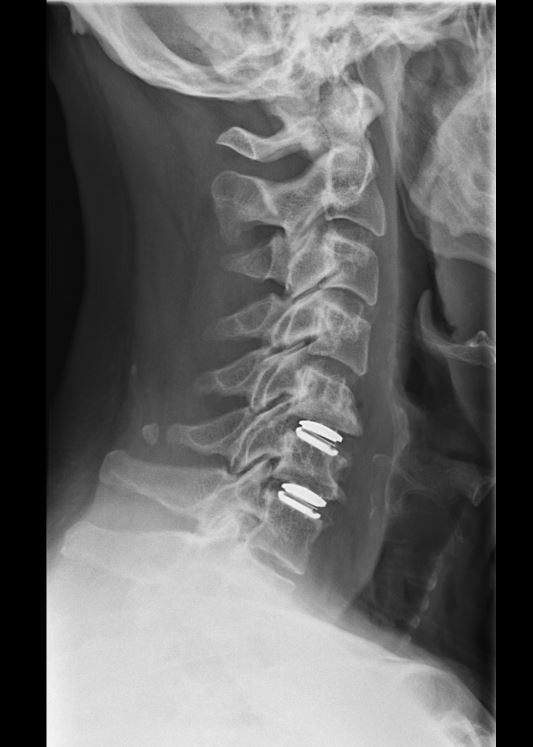

Ο στόχος της χειρουργικής επέμβασης είναι η αποσυμπίεση των νεύρων και του νωτιαίου μυελού με αφαίρεση του κατεστραμμένου μεσοσπονδύλιου δίσκου. Αυτό βελτιώνει τα συμπτώματα του νευρικού πόνου και του πόνου στον αυχένα. Μόλις αφαιρεθεί ο δίσκος και τα νεύρα δεν συμπιέζονται πλέον, στη θέση του δίσκου εισάγεται ένα ειδικό μόσχευμα για τη διατήρηση της κίνησης (τεχνητός δίσκος). Ο τεχνητός δίσκος λειτουργεί σχεδόν όπως ο κανονικός μεσοσπονδύλιος δίσκος (Εικόνα 4).